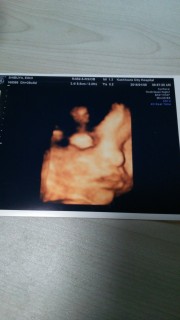

写真:35w5d:ぽんさん:2445g

口がパパ似の女の子で、推定体重は2445グラムと順調。先生からは、もうすぐ臨月だし、 いつ生まれてきても大丈夫と言われました。 早く、元気に生まれてきて欲しいなぁ。